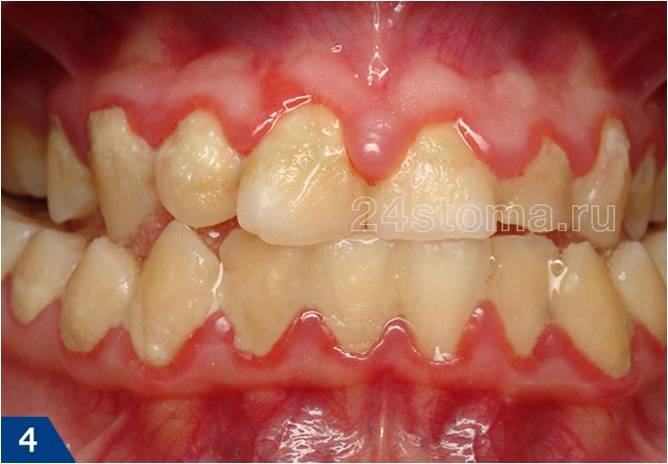

Заболевание пародонта – ответ организма на бактериальную инвазию

Вид больных и протезированых зубов, вы хотите себе такие зубы уже в молодом возрасте.

Общим элементом у всех этих заболеваний есть ВОСПАЛЕНИЕ (в отдельных случаях гноетечение из пародонтальных карманов) → «продлема»: